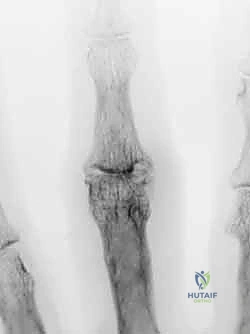

تشوه العروة هو حالة يظهر فيها الإصبع مثنياً عند المفصل الأوسط (PIP) ومفروداً بشكل مفرط عند المفصل الأخير (DIP). سُمي بهذا الاسم لأن التمزق الذي يحدث في الوتر المركزي يخلق فجوة (تشبه عروة القميص) تنزلق من خلالها عظمة المفصل الأوسط، مما يثبت الإصبع في هذا الوضع المعوج.

(ملاحظة: المسار الفعلي للصورة: /media/hutaif_opertive/hutaif-ch62-operative-recon-p2673-3f79ca.webp)

الأعراض والمؤشرات السريرية

- ألم وتورم حاد فوق المفصل الأوسط (PIP) مباشرة بعد الإصابة.

- عدم القدرة على فرد المفصل الأوسط للإصبع بشكل إرادي.

- مع مرور الوقت (أسابيع إلى أشهر)، يتطور التشوه الكلاسيكي: انثناء المفصل الأوسط وفرط استقامة المفصل الأخير.

- تيبس المفصل وفقدان المرونة إذا لم يتم العلاج مبكراً.